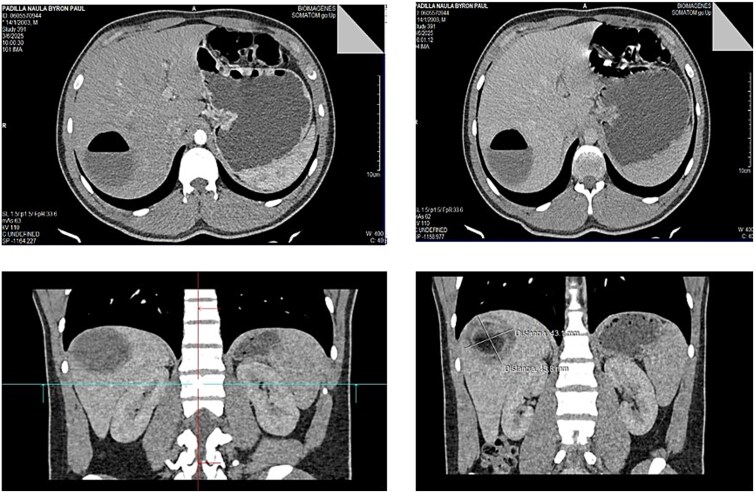

由细粒棘球绦虫引起的肝包虫病在流行地区仍然很流行。手术是治疗的基石,尽管在过去的十年中,腹腔镜方法在选定的病例中获得了突出的地位。我们提出一个病例的加尔比II型肝包虫囊肿成功地通过腹腔镜治疗。19岁男性,来自农村流行地区,表现为右上腹部疼痛。影像学显示肝后段VII有Gharbi 2型包虫囊肿。腹腔镜下对囊肿内容物进行了严格的预防措施,以避免播散。患者预后良好,无并发症。在经验丰富的中心,腹腔镜为没有胆道通信的周围囊肿提供了安全的选择。适当的患者选择和技术熟练程度对于最小化风险至关重要。本报告强调了在精心挑选的患者中腹腔镜治疗Gharbi II型囊肿的可行性,并说明了腹腔镜作为PAIR失败后的抢救策略的作用。

Hepatic hydatidosis, caused by Echinococcus granulosus, remains prevalent in endemic regions. Surgery is the cornerstone of treatment, although laparoscopic approaches have gained prominence in selected cases in the past decade. We present a case of a Gharbi-type II hepatic hydatid cyst successfully treated via laparoscopy. A 19-year-old man from a rural endemic area, presented with right upper quadrant pain. Imaging revealed a Gharbi type 2 hydatid cyst in the posterior segment VII of the liver. Laparoscopic evacuation of the cyst content was performed with strict preventive measures to avoid dissemination. The patient had a favorable outcome without complications. Laparoscopy offers a safe alternative for peripheral cysts without biliary communication and in experienced centers. Proper patient selection and technical proficiency are essential to minimize risks. This report highlights the feasibility of laparoscopic management of Gharbi type II cysts in carefully selected patients and illustrates the role of laparoscopy as a salvage strategy following failed PAIR.